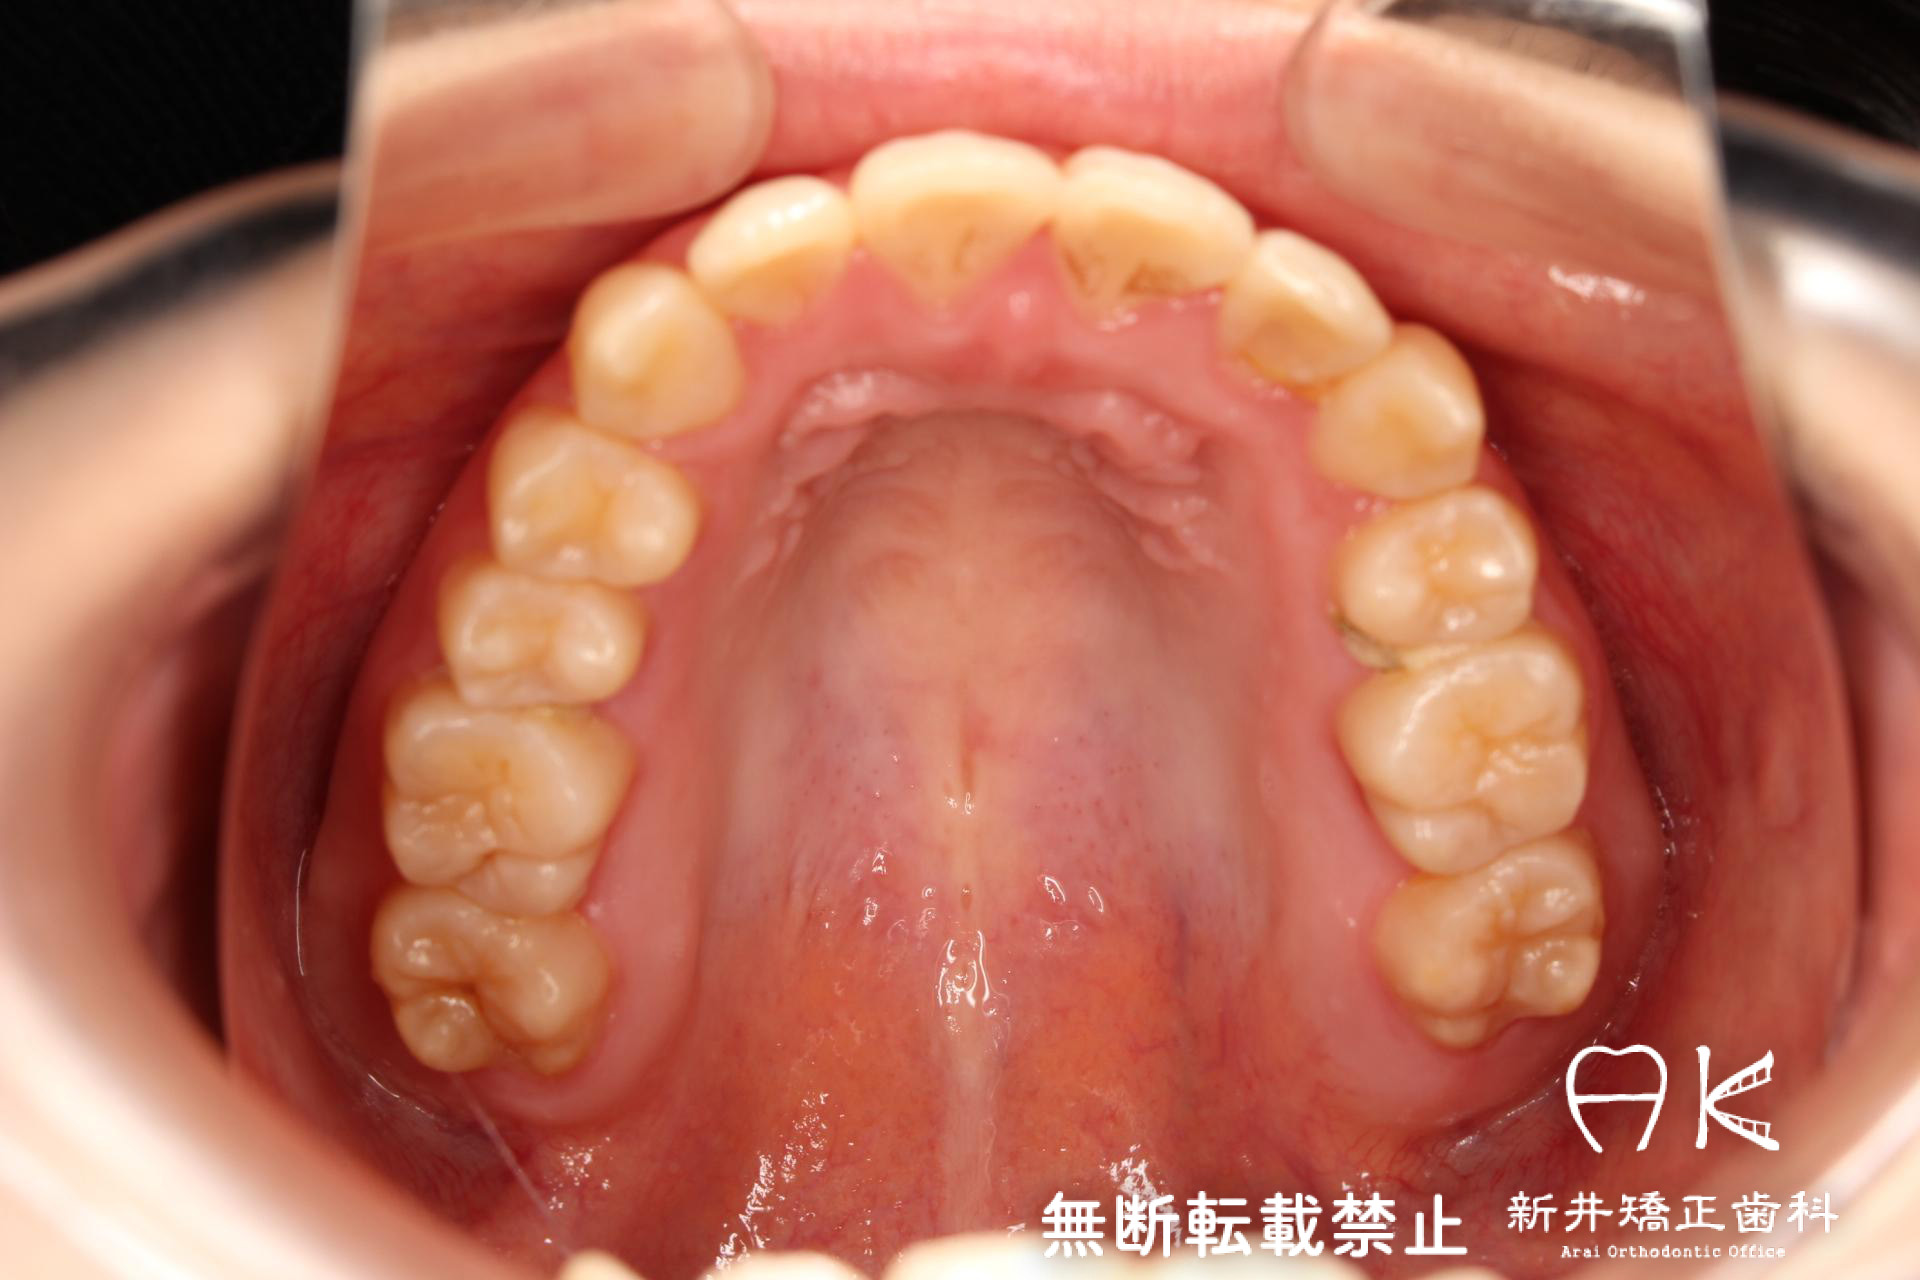

叢生(ガチャ歯・八重歯)と正中のずれの治療

| 症状・診断名 | 叢生 |

| 治療後 | 前歯から奥歯まで全体的に緊密な咬み合わせになっています。 かみ合わせだけでなく、綺麗な歯並びにより機能と審美の両面が改善しました。 ガチャ歯の状態が改善し、食べ物が引っかかることも無くなり、歯ブラシもしやすくなりました。 |